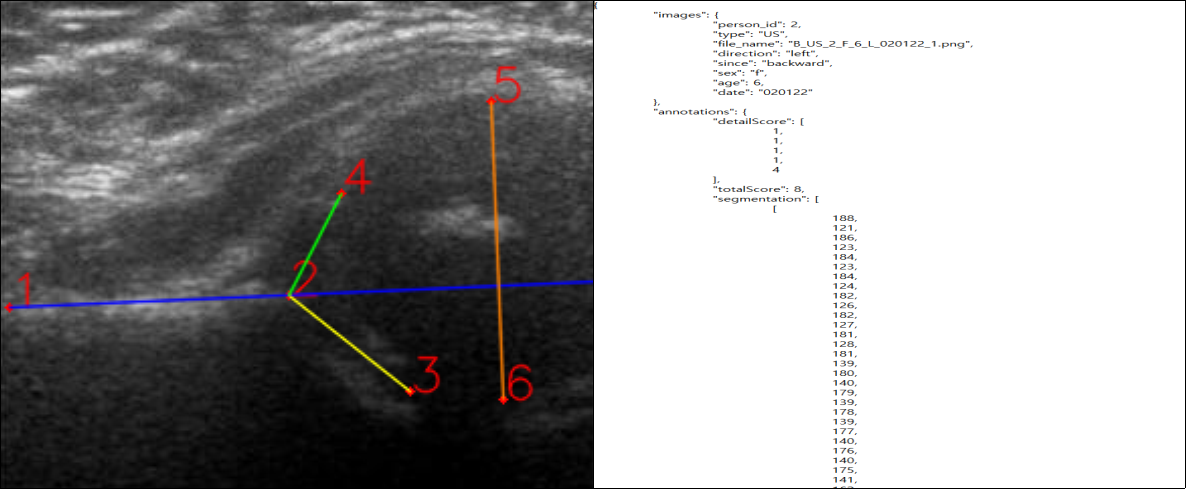

3. 라벨링 데이터 구조(초음파)

| 초음파 | |

5. 어노테이션 포맷(초음파)

| 항목명 | 타입 | 필수여부 | 설명 | 범위 |

|---|---|---|---|---|

| image | object | |||

| person_id | number | Y | 비식별화된 환자 id | |

| type | string | Y | 초음파 | US |

| file_name | string | Y | 파일 이름 | |

| direction | string | Y | 좌,우 | left,"right" |

| since | string | Y | 전/후향적 | backward, "forward" |

| sex | string | Y | 성별 | “m”,“f” |

| age | number | Y | 월령 | 0~18 |

| date | string | Y | 검사일자 | yymmdd |

| annotations | object | |||

| detailScore | array | Y | ilium, labrum, traiated cartilage, femoral head, gross configuration |

0~4 |

| totalScore | number | Y | 총점 | 0~10 |

| segmentation | array | |||

| keypoints | object | |||

| keypoint | array | 키포인트 좌표 | ||

| num_keypoints | number | 키포인트 개수 | 6 | |

| containment | number | (b/a+b)*100 | 0~100 | |

| diagnose | string | Y | 이상,정상 여부 | “normal”, “abnormal” |

| a | object | |||

| angle | number | 알파 각도 | 0~90 | |

| diagnose | string | Y | 알파 각도로 판단된 질환 | normal, "mild Dysplasia", "moderate dysplasia", "severe dysplasia“ |

| b | object | |||

| angle | number | 베타 각도 | 0~90 | |

| diagnose | string | Y | 베타 각도로 판단된 질환 | normal, "mild Dysplasia", "moderate dysplasia", "severe dysplasia“ |